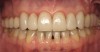

Figure 1 and Figure 2 Preoperative photographs. The patient felt self-conscious about his smile, after 25 years of acid erosion, and wanted them restored to an appropriate size for function and esthetics. Note the posterior teeth are barely visible when smiling, and his upper lip support is deficient.

Figure 1

Figure 2

In June 2013, a 47-year-old man presented to the author’s office with the chief complaint, of having lost a lot of enamel after 25 years of suffering from acid reflux. He was interested protecting and rebuilding his teeth without reducing much more tooth structure (Figure 1 through Figure 9). He was also concerned about trapping food between teeth Nos. 2 and 3. The patient had seen an endodontist for a swelling in the upper right area between the molars, which was drained but did not require root canal therapy, and the author advised him to see the periodontist for a consultation to discuss all esthetic options and treatment plan for an implant to replace his missing upper left first molar. The author decided to take records for an esthetic wax-up to determine how much he would need to open up the vertical dimension of occlusion (VDO) in order to create a more ideal smile using the conservative biomimetic principles and achieving better facial harmony.

When viewing his maxillary teeth from an occlusal and lingual view, one can see the erosion and wear (Figure 4, Figure 6, and Figure 7), and it becomes evident just how collapsed he actually is. This patient shows more teeth on his left side and less on the right when smiling, and the shortness and color of his teeth contributes to a definite aging of his smile. Additionally, his lips appear less full without the lip support of the lost tooth structure. The patient had Class I molar relationships on both the right and left sides, and a posterior open bite on his right side in the area of teeth Nos. 4 through 6 (Figure 8 and Figure 9). There was no crowding evident and both arches were found to have lingually inclined teeth, which may have contributed to his wear. It was also noted that his posterior teeth were worn down with a very flat anatomy and lacked proper functional guidance.